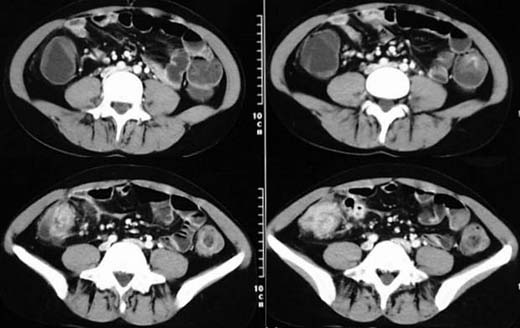

Patientin, 26 Jahre alt, Schmerzen im rechten Unterbauch.

Weichteildichte

Verschattung

des Epitympanum und knöcherne

Destruktion des Innenohres auf der linken Seite (oberes Bild).

Ebenfalls weichteildichte Verschattung des Mesotympanum links ohne Destruktion

der Gehörknöchelchenkette (mittleren Bild). In der koronaren Rekonstruktion

ist die knöcherne Destruktion

des Tegmen tympani zu erkennen (mittleres Bild)

sowie das Cholesteatom

im Meso- und Epitympanum (unteres Bild).

DIAGNOSE:

Cholesteatom